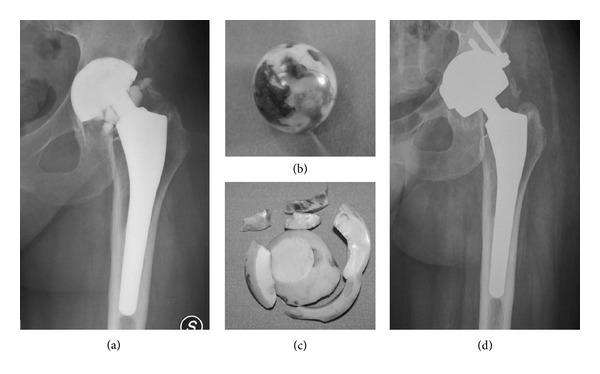

Fracture of ceramic bearing surfaces following total hip replacement: a systematic review.

Ceramic bearing surfaces are increasingly used for total hip replacement, notwithstanding that concern is still related to ceramic brittleness and its possible mechanical failure. The aim of this systematic review is to answer three questions: (1) Are there risk factors for ceramic component fracture following total hip replacement? (2) Is it possible to perform an early diagnosis of ceramic component failure before catastrophic fracture occurs? (3) Is it possible to draw guidelines for revision surgery after ceramic components failure? A PubMed and Google Scholar search was performed and reference citations from publications identified in the literature search were reviewed. The use of 28 mm short-neck femoral head carries an increased risk of fracture. Acetabular component malposition might increase the risk of ceramic liner fractures. Synovial fluid microanalysis and CT scan are promising in early diagnosis of ceramic head and liner failure. Early revision is suggested in case of component failure; no consensus exists about the better coupling for revision surgery. Ceramic brittleness remains a major concern. Due to the increased number of ceramic on ceramic implants, more revision surgeries and reports on ceramic components failure are expected in the future. An algorithm of diagnosis and treatment for ceramic hip failure is proposed.